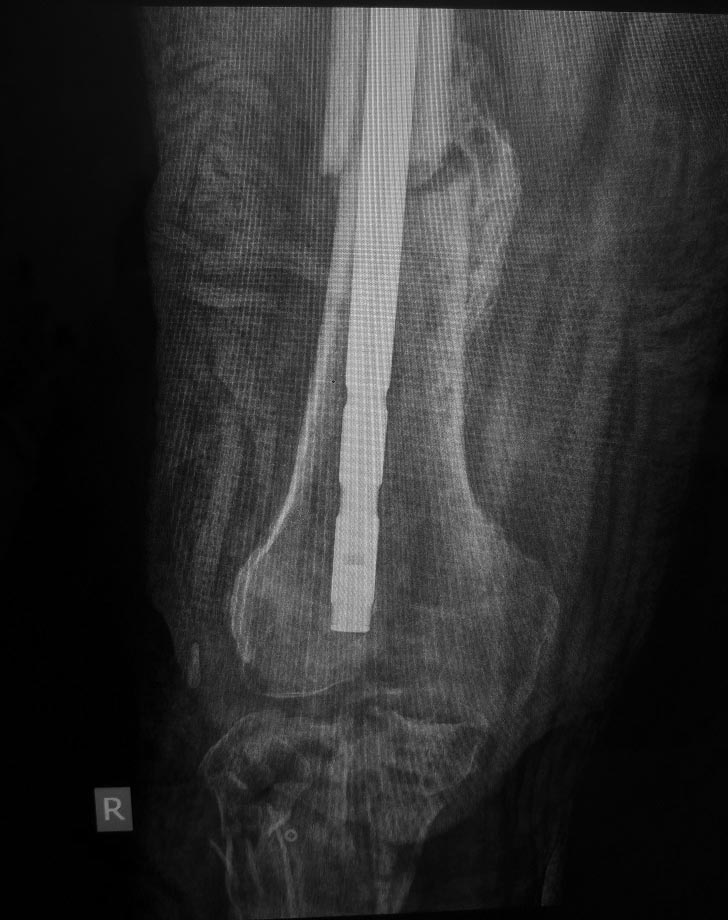

Нужен совет - хронический остеомиелит проксимального отдела голени, ложный сустав с/3-н/3 бедренной кости

Вот такой случай. У пациента хронический остеомиелит проксимального отдела голени. Ложный сустав с/3-н/3 бедренной кости. Был спице-стержневой АВФ бедро-голень. Прям на штифте.

1. Резекция проксимального отдела голени 8 см приблизительно, собственной связки надколенника, самого надколенника?. Промывание;

2. Удаление штифта;

3. наложение АВФ спице-стрежневого на бедро и голень.

Еще есть мысль со спейсером, но не знаю????